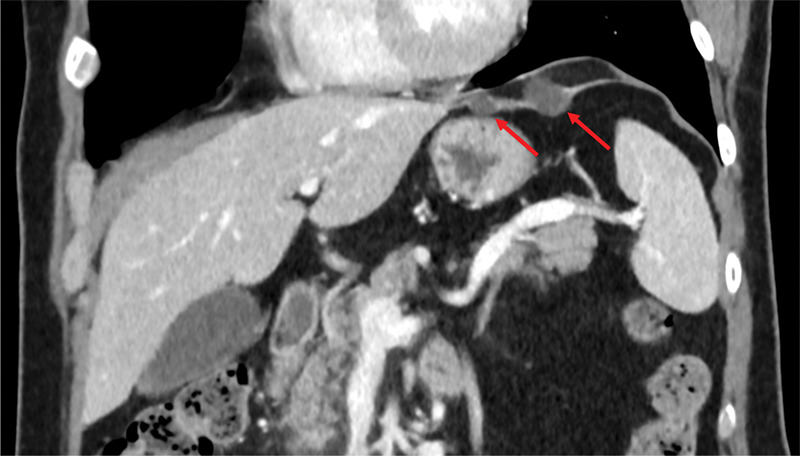

Hepatic Cysts in the Left Triangular Ligament: A Rare Finding with Potential Diagnostic Challenges.

肝囊肿在左三角韧带:一个罕见的发现与潜在的诊断挑战。